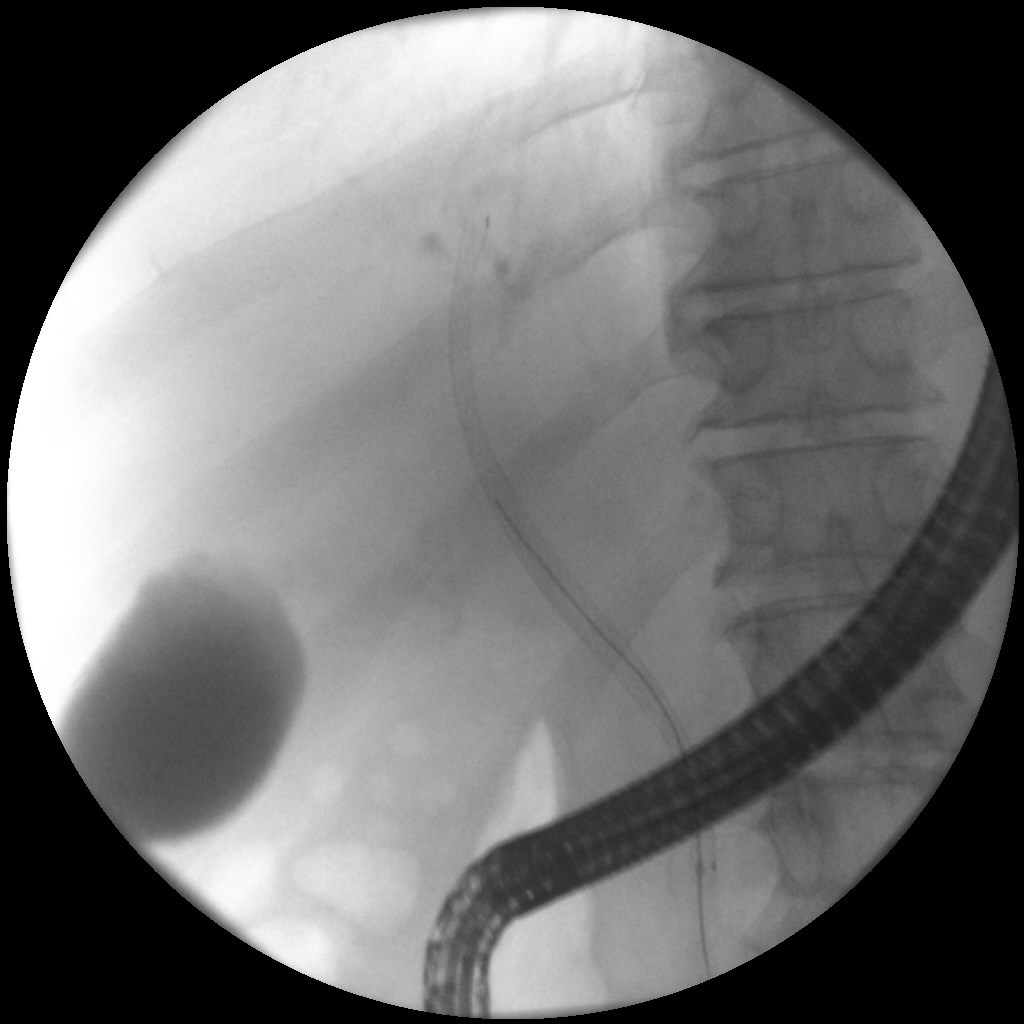

ERCP

Άνδρας 61 ετών με ανώδυνο αποφρακτικό ίκτερο υποβλήθηκε σε μαγνητική τομογραφία που έδειξε διάταση ενδοηπατικών χοληφόρων με στένωση του κοινού ηπατικού πόρου και της συμβολής του δεξιού και αριστερού ηπατικού πόρου, εικόνα συμβατή με χολαγγειοκαρκίνωμα της πύλης του ήπατος (όγκος Klatskin, Bismuth IV). Επίσης συνυπήρχε θρόμβωση πυλαίας φλέβας, ασκιτικό υγρό και ευμεγέθεις λεμφαδένες πέριξ της κεφαλής του παγκρέατος και στον ηπατοδωδεκαδακτυλικό σύνδεσμο. Το νεόπλασμα κρίθηκε ανεγχείρητο μετά από συζήτηση σε συμβούλιο πολλαπλών ειδικοτήτων και ο ασθενής υποβλήθηκε σε ενδοσκοπική παλίνδρομη χολαγγειο-παγκρεατογραφία (ERCP) για αποσυμφόρηση του ικτέρου. Στην ERCP έγινε λήψη κυττάρων από την περιοχή της στένωσης με βούρτσα κυτταρολογικής, διαστολή της στένωσης με μπαλόνι και επιτυχής τοποθέτηση ακάλυπτου, μεταλλικού stent μήκους 10εκ. Μετά την ERCP, ο ασθενής βελτιώθηκε κλινικά με σημαντική υποχώρηση του ικτέρου.